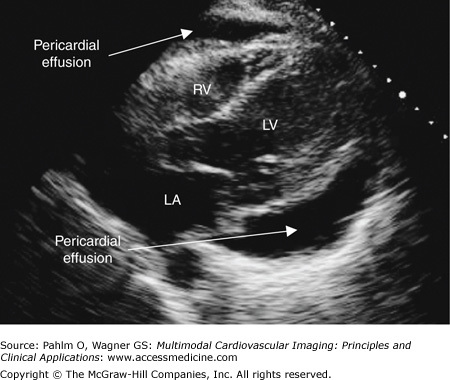

Pericardial Effusion on Transthoracic Echocardiogram

Pericardial effusion. Subxiphoid/subcostal image of a large pericardial effusion, approximately 2.0 cm. LA, left atrium; LV, left ventricle; RV, right ventricle.